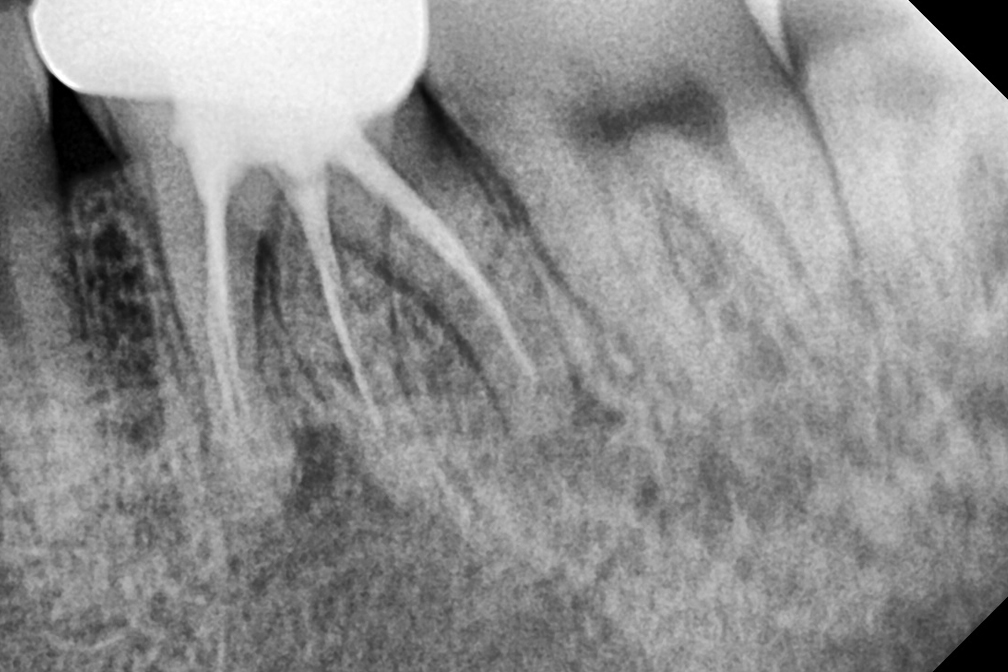

재신경치료

Before 2025년 9월 16일